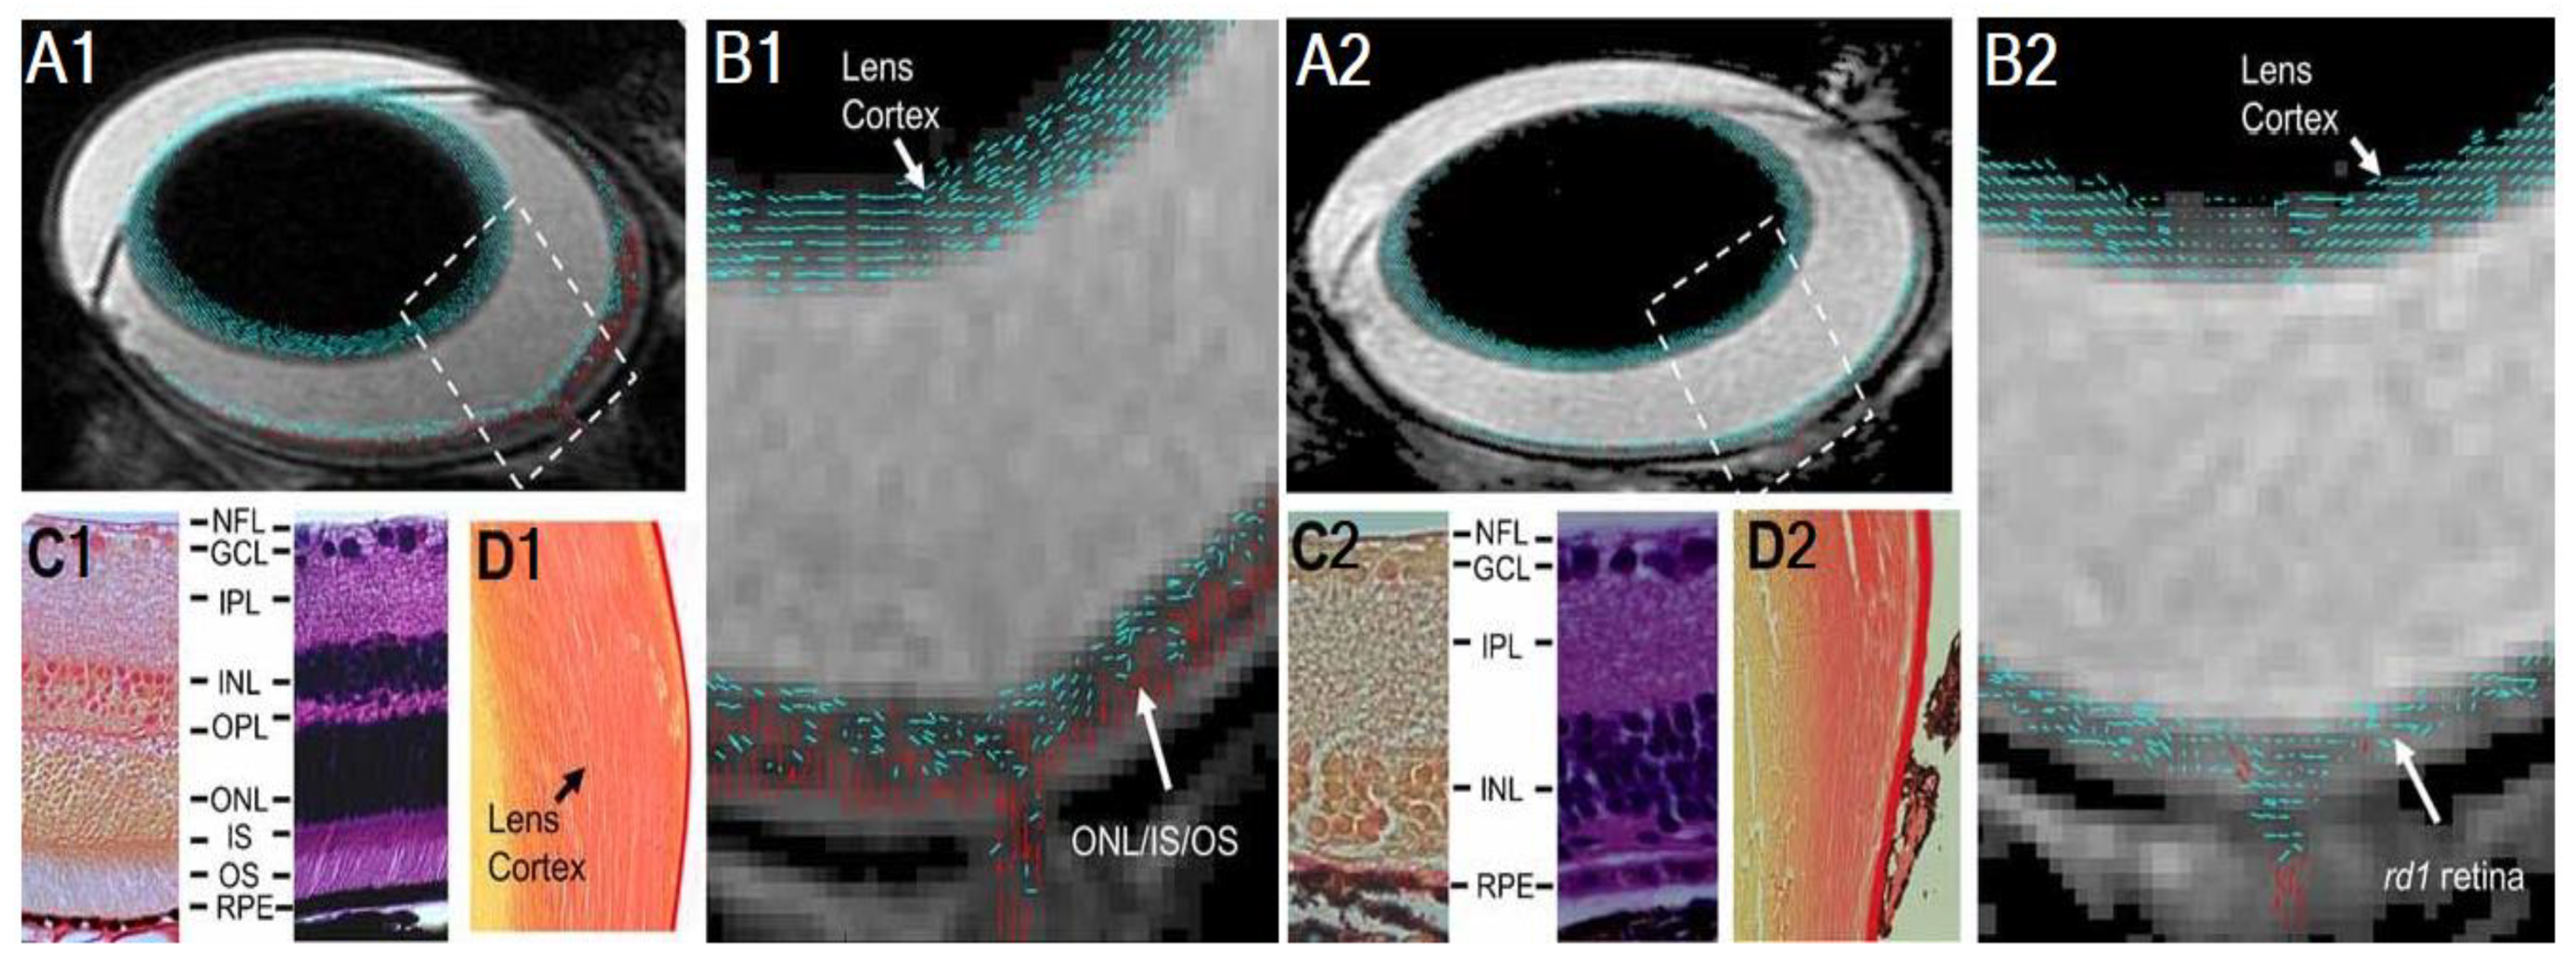

2.2. Anatomical MRI in Glaucona

- Cheng, H.; Nair, G.; Walker, T.A.; Kim, M.K.; Pardue, M.T.; Thulé, P.M.; Olson, D.E.; Duong, T.Q. Structural and functional MRI reveals multiple retinal layers. Proc. Natl. Acad. Sci. USA 2006, 103, 17525–17530. [Google Scholar] [CrossRef] [PubMed] [Green Version]

- Li, G.; De La Garza, B.; Shih, Y.-Y.I.; Muir, E.R.; Duong, T.Q. Layer-specific blood-flow MRI of retinitis pigmentosa in RCS rats. Exp. Eye Res. 2012, 101, 90–96. [Google Scholar] [CrossRef] [PubMed] [Green Version]

- Chen, J.; Wang, Q.; Chen, S.; Wickline, S.A.; Song, S.-K. In vivo diffusion tensor MRI of the mouse retina: A noninvasive visualization of tissue organization. NMR Biomed. 2010, 24, 447–451. [Google Scholar] [CrossRef] [PubMed]